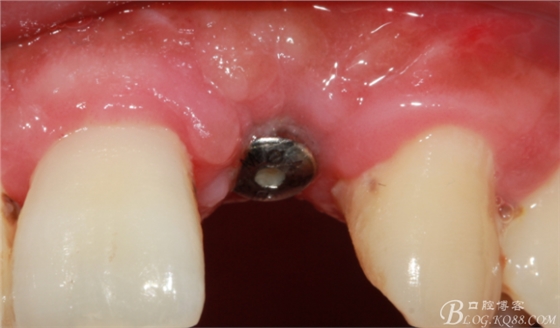

事實(shí)證明,我的做法沒有錯(cuò)誤,一個(gè)月后,軟組織健康愈合。鄰牙軟組織沒有退縮。

再次翻瓣。